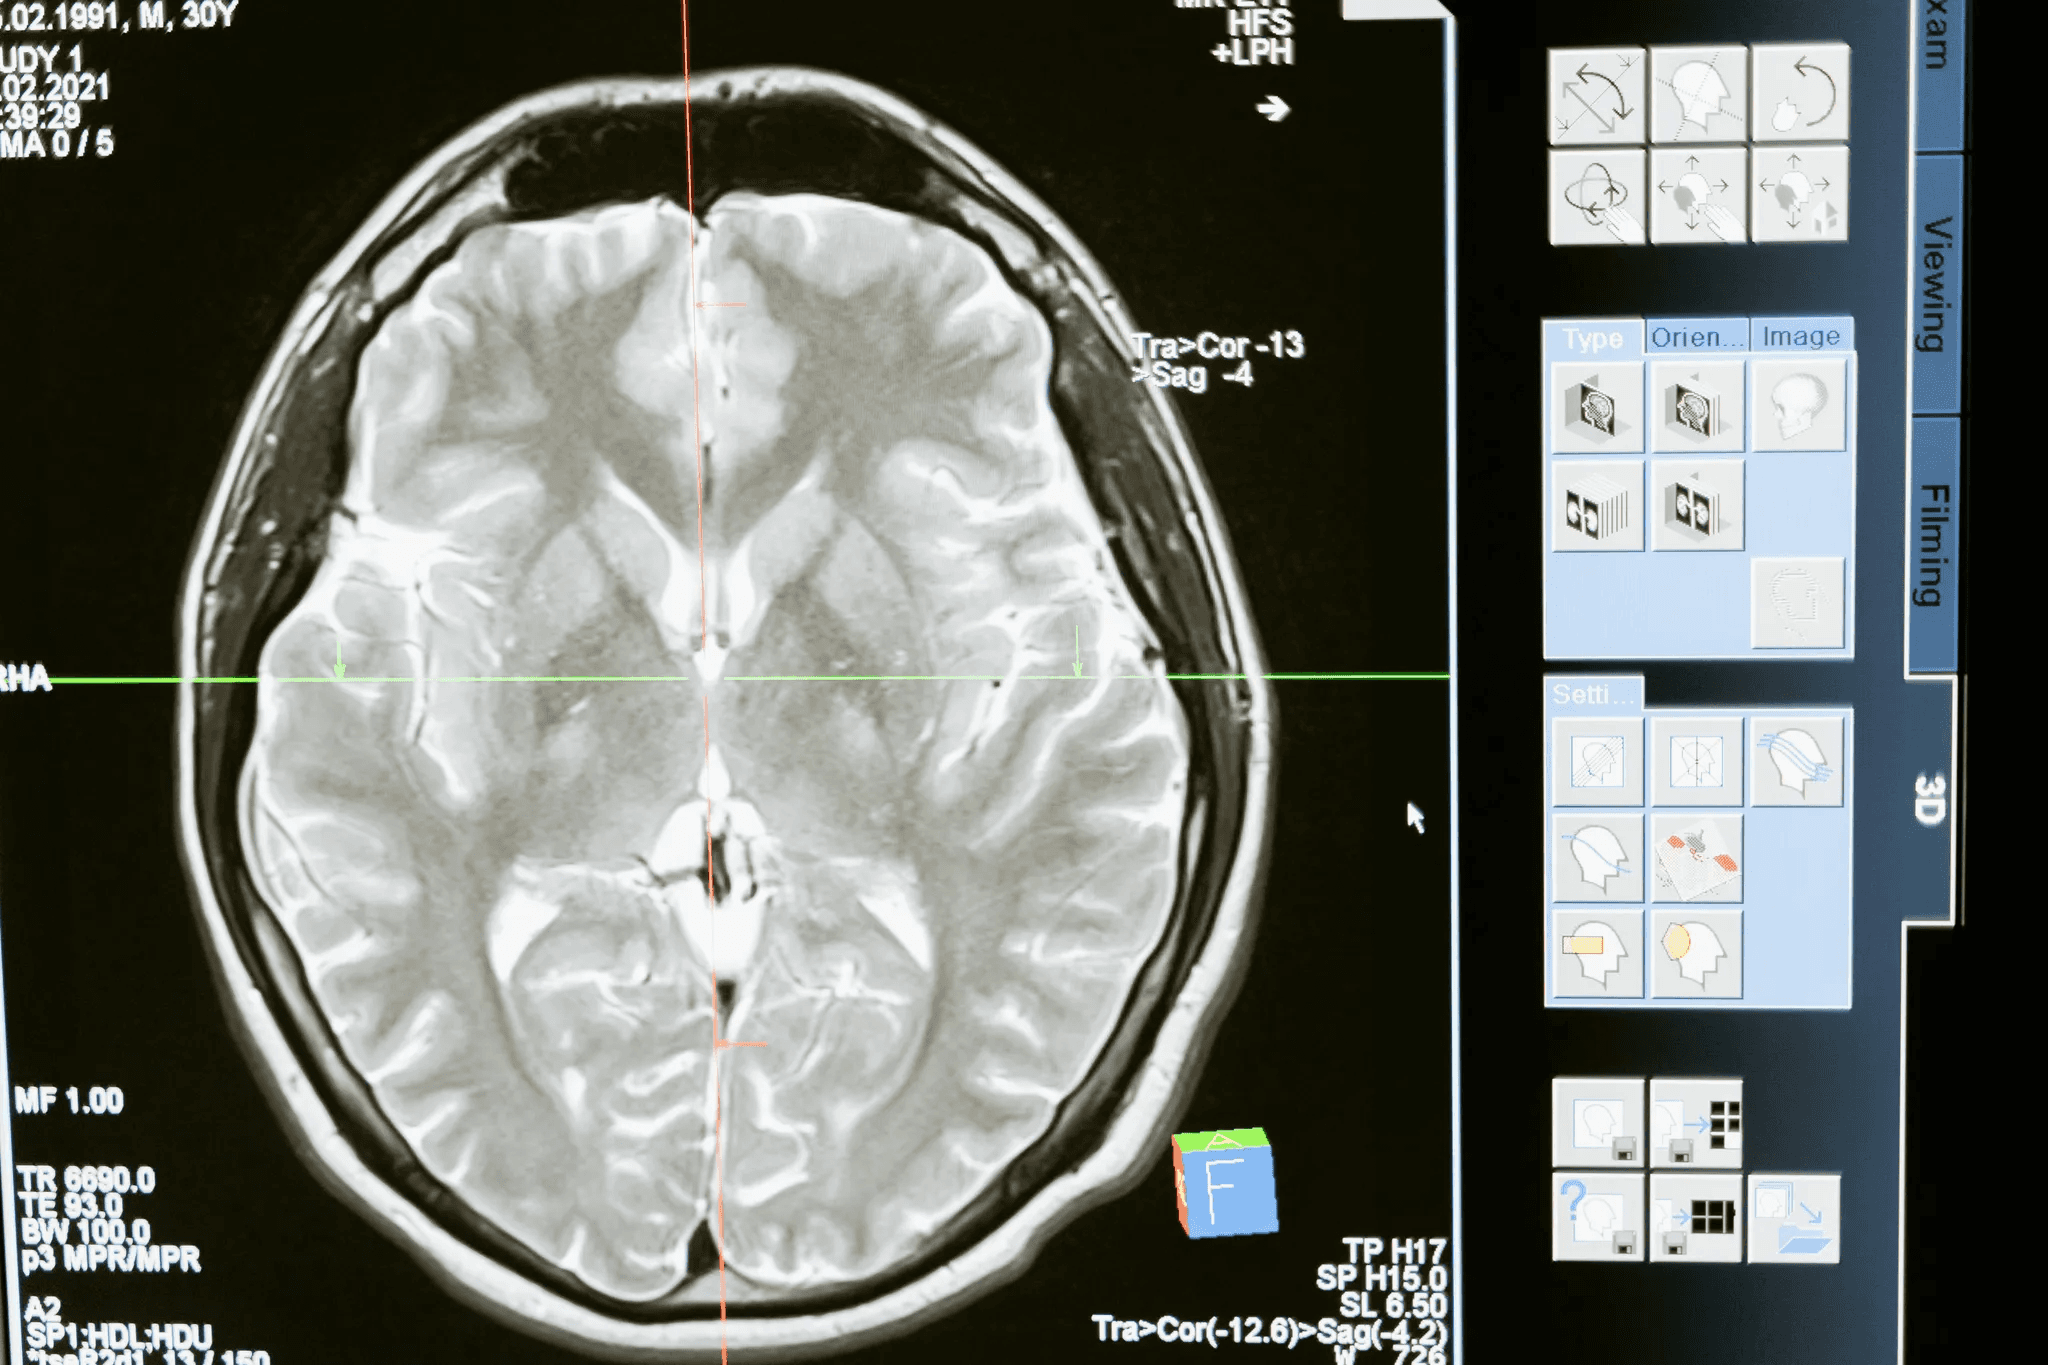

Neurology has seen similarly compelling results. A 2025 multicenter prospective study conducted across 67 inpatient medical organizations in Moscow evaluated AI performance in detecting intracranial hemorrhage (ICH) on brain CT across more than 3,400 studies. The study demonstrated that AI-assisted radiologists outperformed both standalone AI and unassisted radiologists, confirming the "augmented clinician" model as the highest-performing configuration for neuroimaging diagnosis. AI stroke diagnosis technology is now being implemented across stroke centers in multiple countries, with the UK committing to nationwide deployment.

Accuracy varies significantly by task and deployment context. AI diagnostic systems have demonstrated 90-95% accuracy for specific, well-defined tasks such as detecting intracranial hemorrhage on brain CT, classifying skin lesions, or identifying diabetic retinopathy from retinal scans.